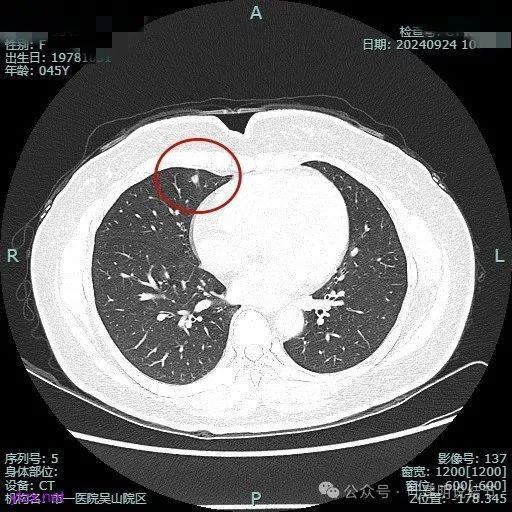

病灶1:

病灶是混合密度,边缘少许淡磨玻璃,灶内不太致密,表面不平,血管征有,但说不上明显异常增粗。

病灶紧贴叶间裂,而且感觉跨过肺叶,部分影响到上叶了,病灶本身密度虽实性为主,但是不太致密,有点松散的感觉。

总体实性部分密度较高,而磨玻璃部分密度较低,且瘤肺边界欠清,关键是跨叶间裂生长,这与肿瘤似乎不容易解释些。

毛刺有但不太锐利,磨玻璃有但偏淡,实性为但不太致密,叶间裂与之关系密切,病灶跨叶生长。

上图显得与肿瘤较为符合,但跨叶生长的话,侵袭力应该较强,可她这病灶较刚发现时进展并不太明显。

上图层面也较符合恶性,血管进入明显,有浅分叶的样子,整体觉得有一定收缩力与膨胀感。

病灶表面不平,混合密度,磨玻璃成分较淡。